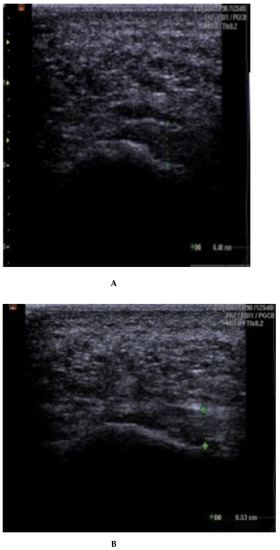

Fascia thickness and echogenicity. All patients had an increased plantar fascia thickness (3.50–8.0 mm) at baseline when measured with MSKUS, and all had hypo-echogenicity. There was a significant difference in the reduction of the plantar fascia thickness between the two groups at 4 weeks follow-up in favor of CSI + TUS (p = 0.004, Table 5), as also shown in Figure A1 and demonstrated in ultrasound images in Figure A2 and Figure A3. At the 12-week follow-up, plantar fascia thickness was significantly higher in the CSI + TUS group (p = 0.012), with an insignificant difference in the decrease between both groups (p = 0.216).

Echogenicity change (Figure A2 and Figure A3) from hypoechoic to iso- or hyperechoic was statistically significant in both groups at 12-week follow-up, but no significant difference was found between the groups (p = 0.208; Table A1).

(A–C): plantar fascia thickness and echogenicity before, after 4 weeks, and 12 weeks follow-up (ESWT). (A). Plantar fascia thickness (0.53 cm) and echogenicity (hypoechoic) before ESWT; Ankles are in 90 dorsiflexion;. Images obtained just medial to the midline, at the proximal end of the plantar fascia, distal to its origin, from the medial tubercle of the calcaneus; Thickness of the plantar fascia was measured from the base of the medial calcaneal tubercle, where a bright echogenic line was easily visible. (B). Plantar fascia thickness (0.51 cm) and echogenicity (hypoechoic) after 4 weeks. (C). Plantar fascia thickness (0.48 cm) and echogenicity (hypo-echoic) after 12 weeks.